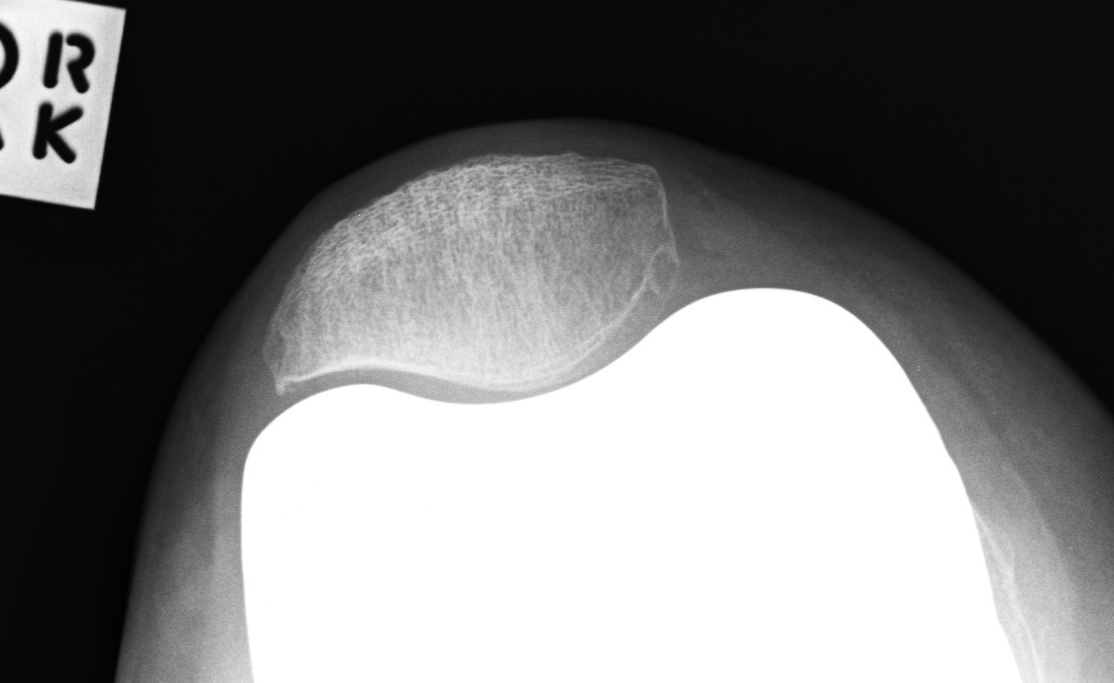

Patella Baja

Problem

- limits flexion

- due to patella impingement on tibia in flexion

Causes

- HTO

- tibial tuberosity transfer

- tibial fracture

Solutions

1. Lower joint line

- cut more tibia, distal femoral augments

2. Resurface patella and place button superiorly

- effectively lengthens the patella tendon

3. Shave anterior surface of PE

4. Trim but don't resurface patella

- resect

- shave off inferior aspect of patella